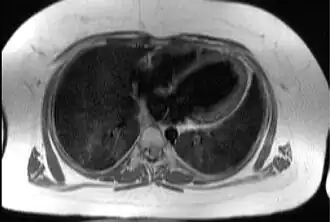

![]() Трансаксиальное изображение грудной клетки на уровне сердца, иллюстрирующее типичную жировую ткань подкожно и эпикардиально у пациента с синдромом Альстрёма. | |